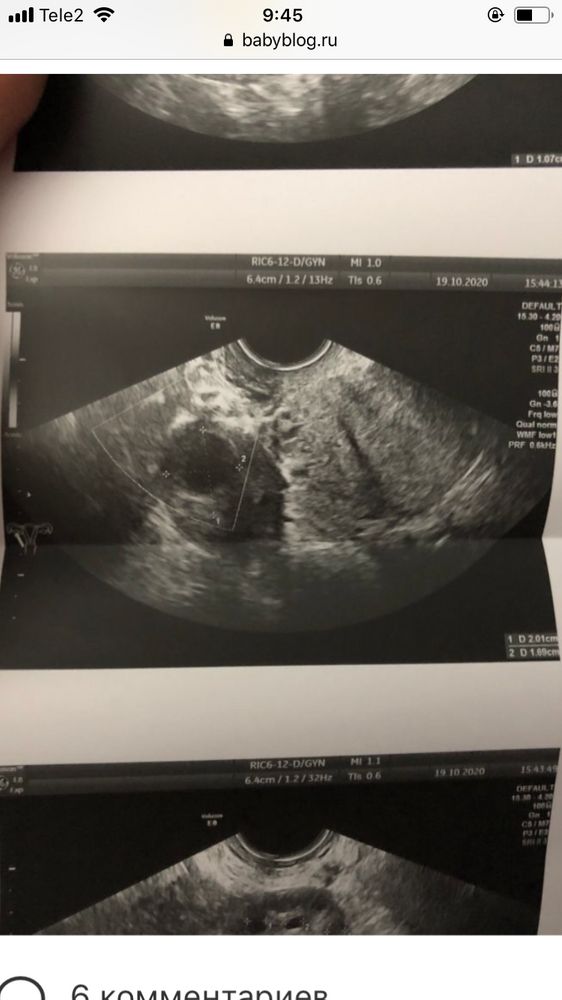

Lisenok, Вот якобы мое жт. Но я сомневаюсь что это оно